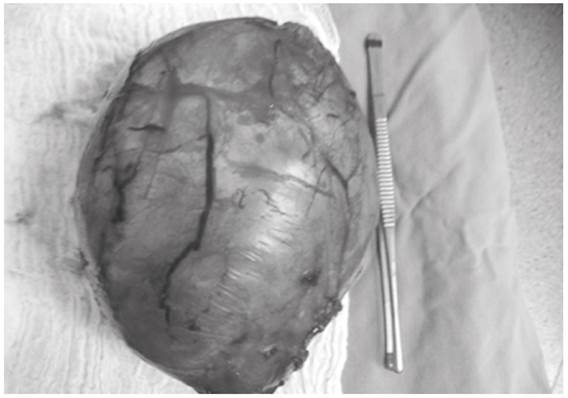

Un mes antes de la cirugía se le inició tratamiento antihipertensivo con telmisartán, amlodipino, clonidina y propanolol, con lo cual se lograron cifras tensionales no superiores a 140/90 mm Hg. Por laparotomía se extrajo una masa vascularizada adherida a la pared posterior (Figura 2), cuyo examen histológico reveló una lesión tumoral compuesta por células poligonales rosadas con cromatina granular dispersa, dispuestas en un patrón alveolar en estroma con tractos delgados fibrovasculares y zonas de hialinización, edema y hemorragias antigua y reciente. Atipia moderada sin necrosis ni mitosis. El tumor estaba rodeado por una cápsula de grosor variable con tinta negra exterior distante de él. Las células tumorales mostraron inmunomarcación positiva para cromogranina y sinaptofisina. El marcador S100 fue positivo en células del estroma. El índice de proliferación Ki67 fue del 3 %.